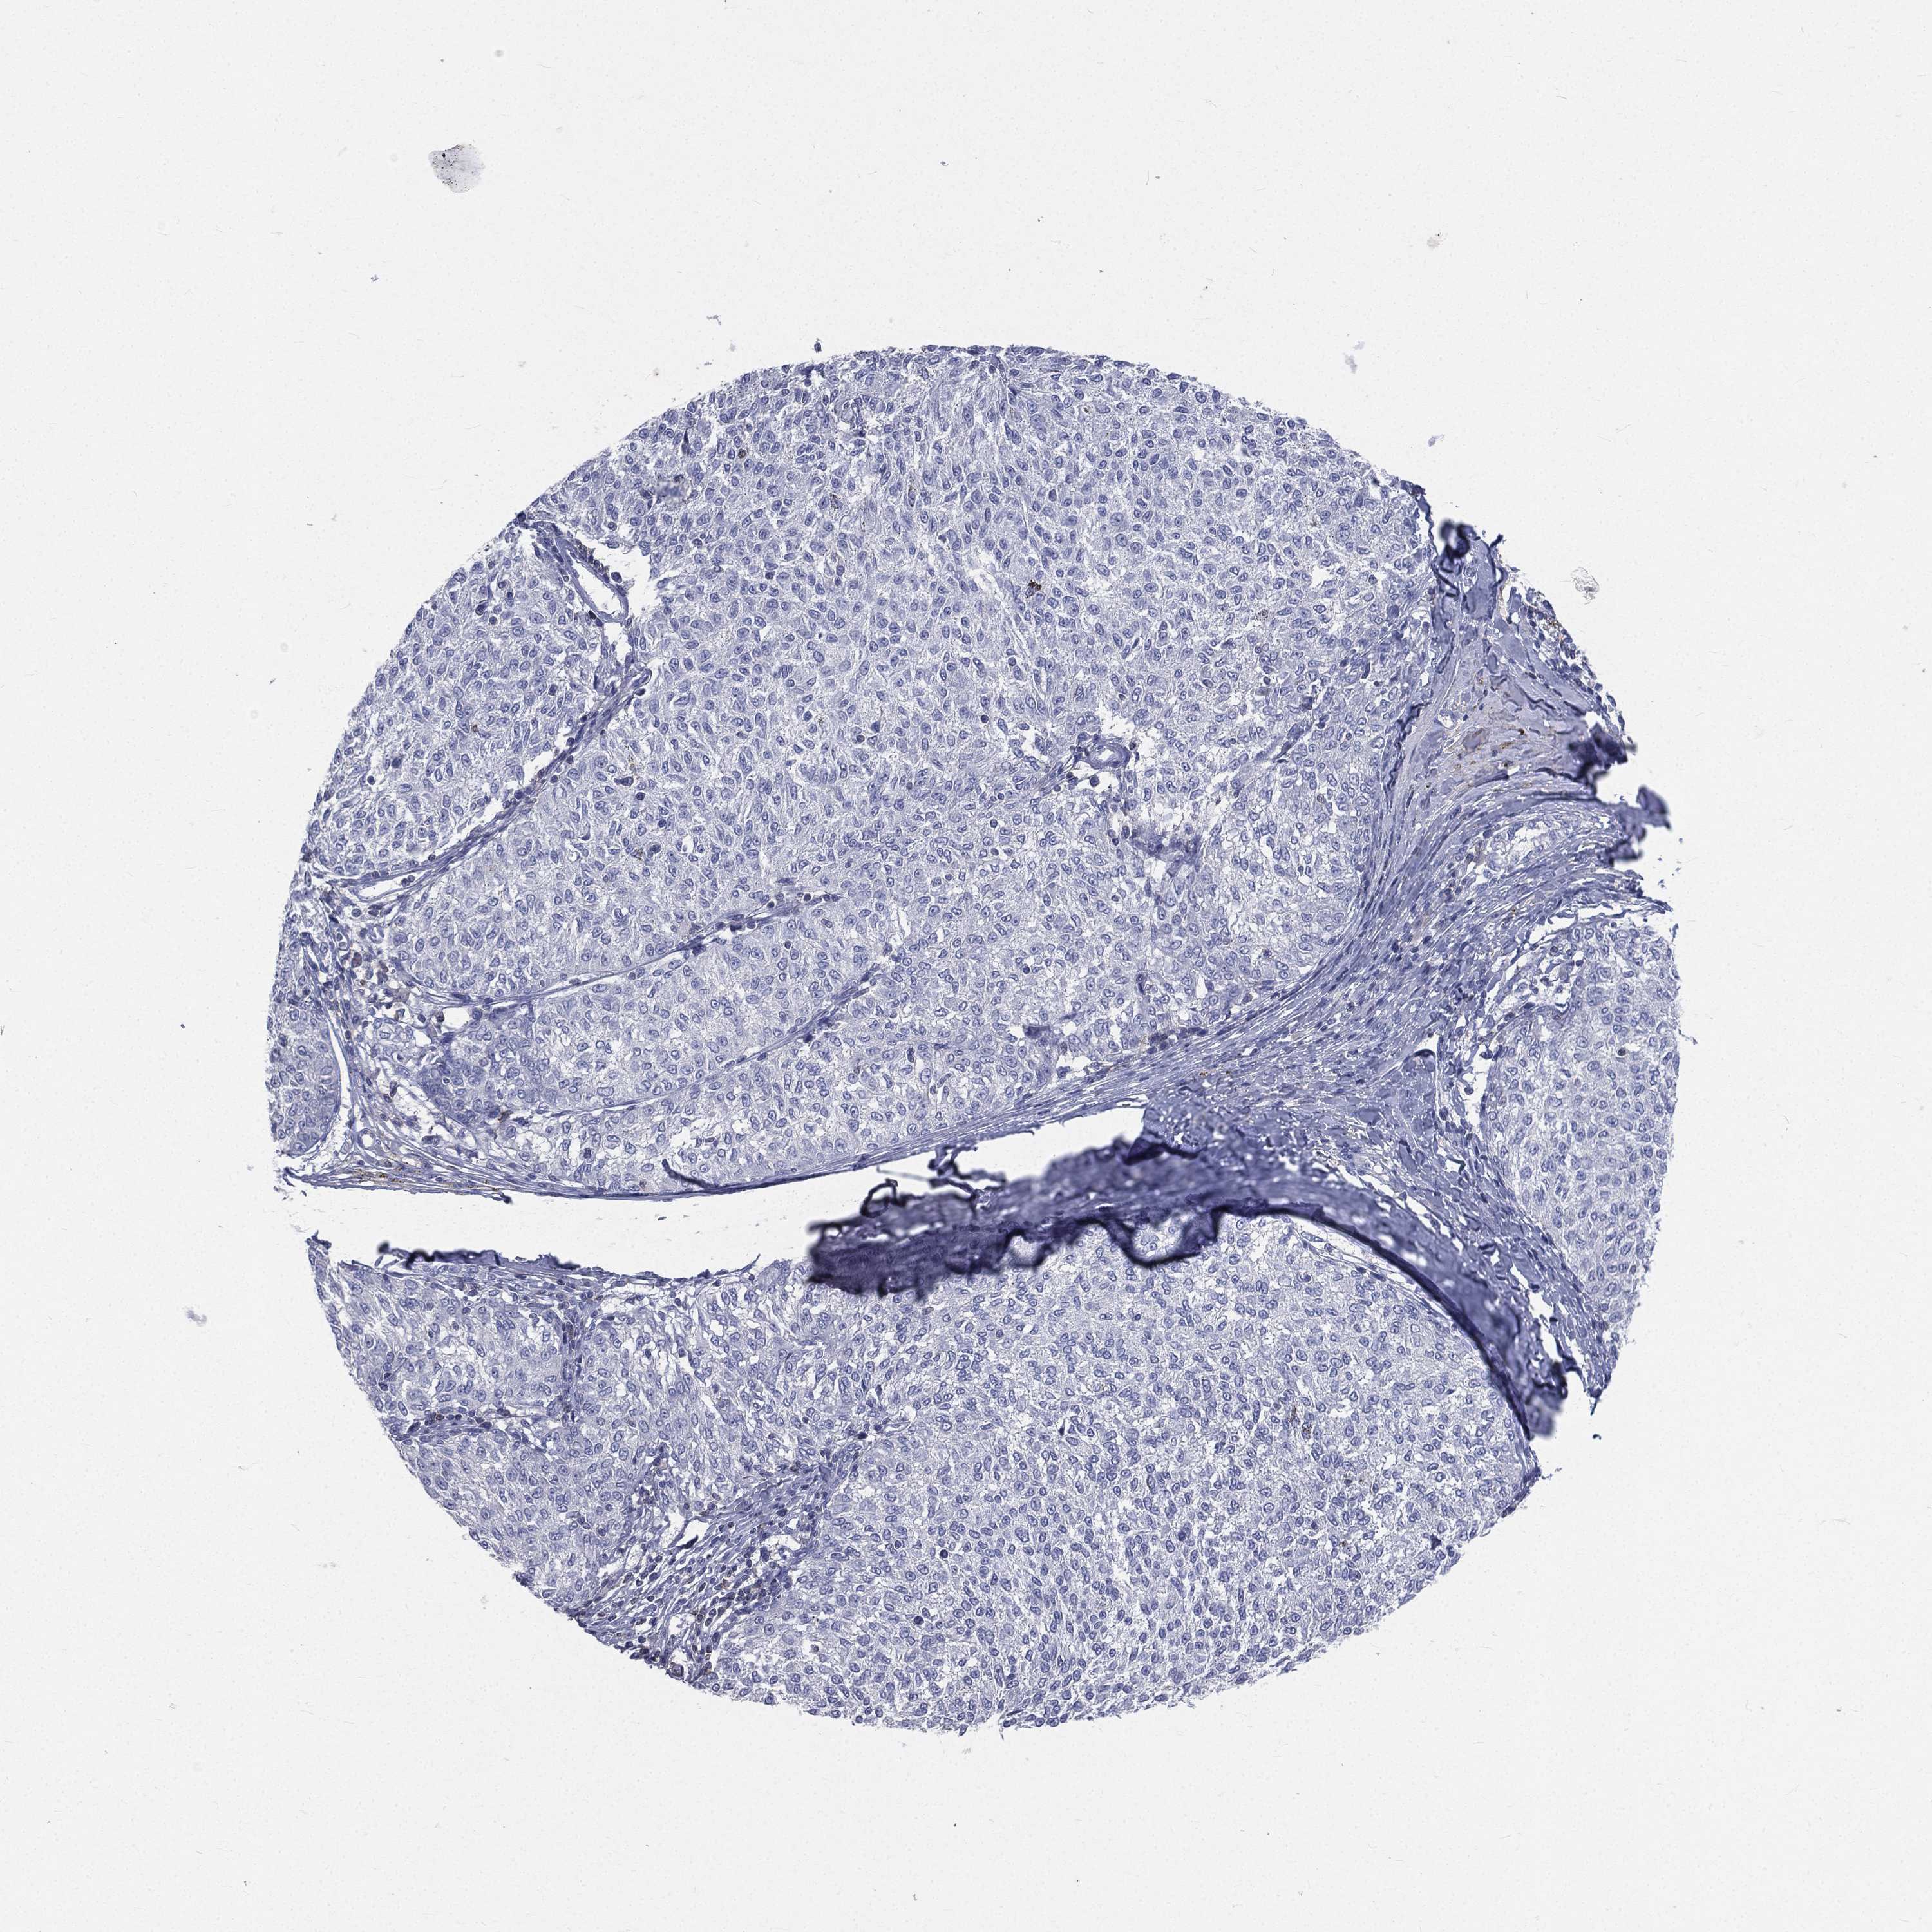

MELANOMA - Protein expressioni

A mouse-over function shows sample information and annotation data. Click on an image to view it in a full screen mode. Samples can be filtered based on level of antibody staining by selecting one or several of the following categories: high, medium, low and not detected. The assay and annotation is described here.

Note that samples used for immunohistochemistry by the Human Protein Atlas do not correspond to samples in the TCGA dataset.

Antibody stainingi

Antibody staining in the annotated cell types in the current human tissue is reported as not detected, low, medium, or high, based on conventional immunohistochemistry profiling in selected tissues. This score is based on the combination of the staining intensity and fraction of stained cells.

Each image is clickable and will lead to virtual microscopy that enables deeper exploration of all samples and also displays staining intensity scores, fraction scores and subcellular localization as well as patient and tissue information for each sample.

Antibody HPA071778

Antibody CAB013055

Malignant melanoma, NOS

Malignant melanoma, Metastatic site

Malignant melanoma in situ